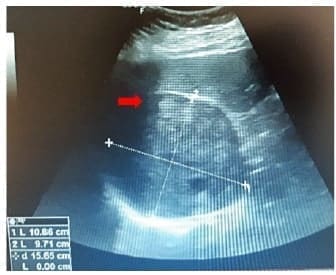

La ecografía abdominal informó una lesión sólida bien definida en espacio hepatorrenal, con ecogenicidad heterogénea, de 11 x 10 cm, en relación con tumor adrenal derecho (figura 1).

Figura 1. Ultrasonografía con evidencia de lesión tumoral en glándula suprarrenal derecha.

Fuente: Hospital Universitario San Vicente Fundación